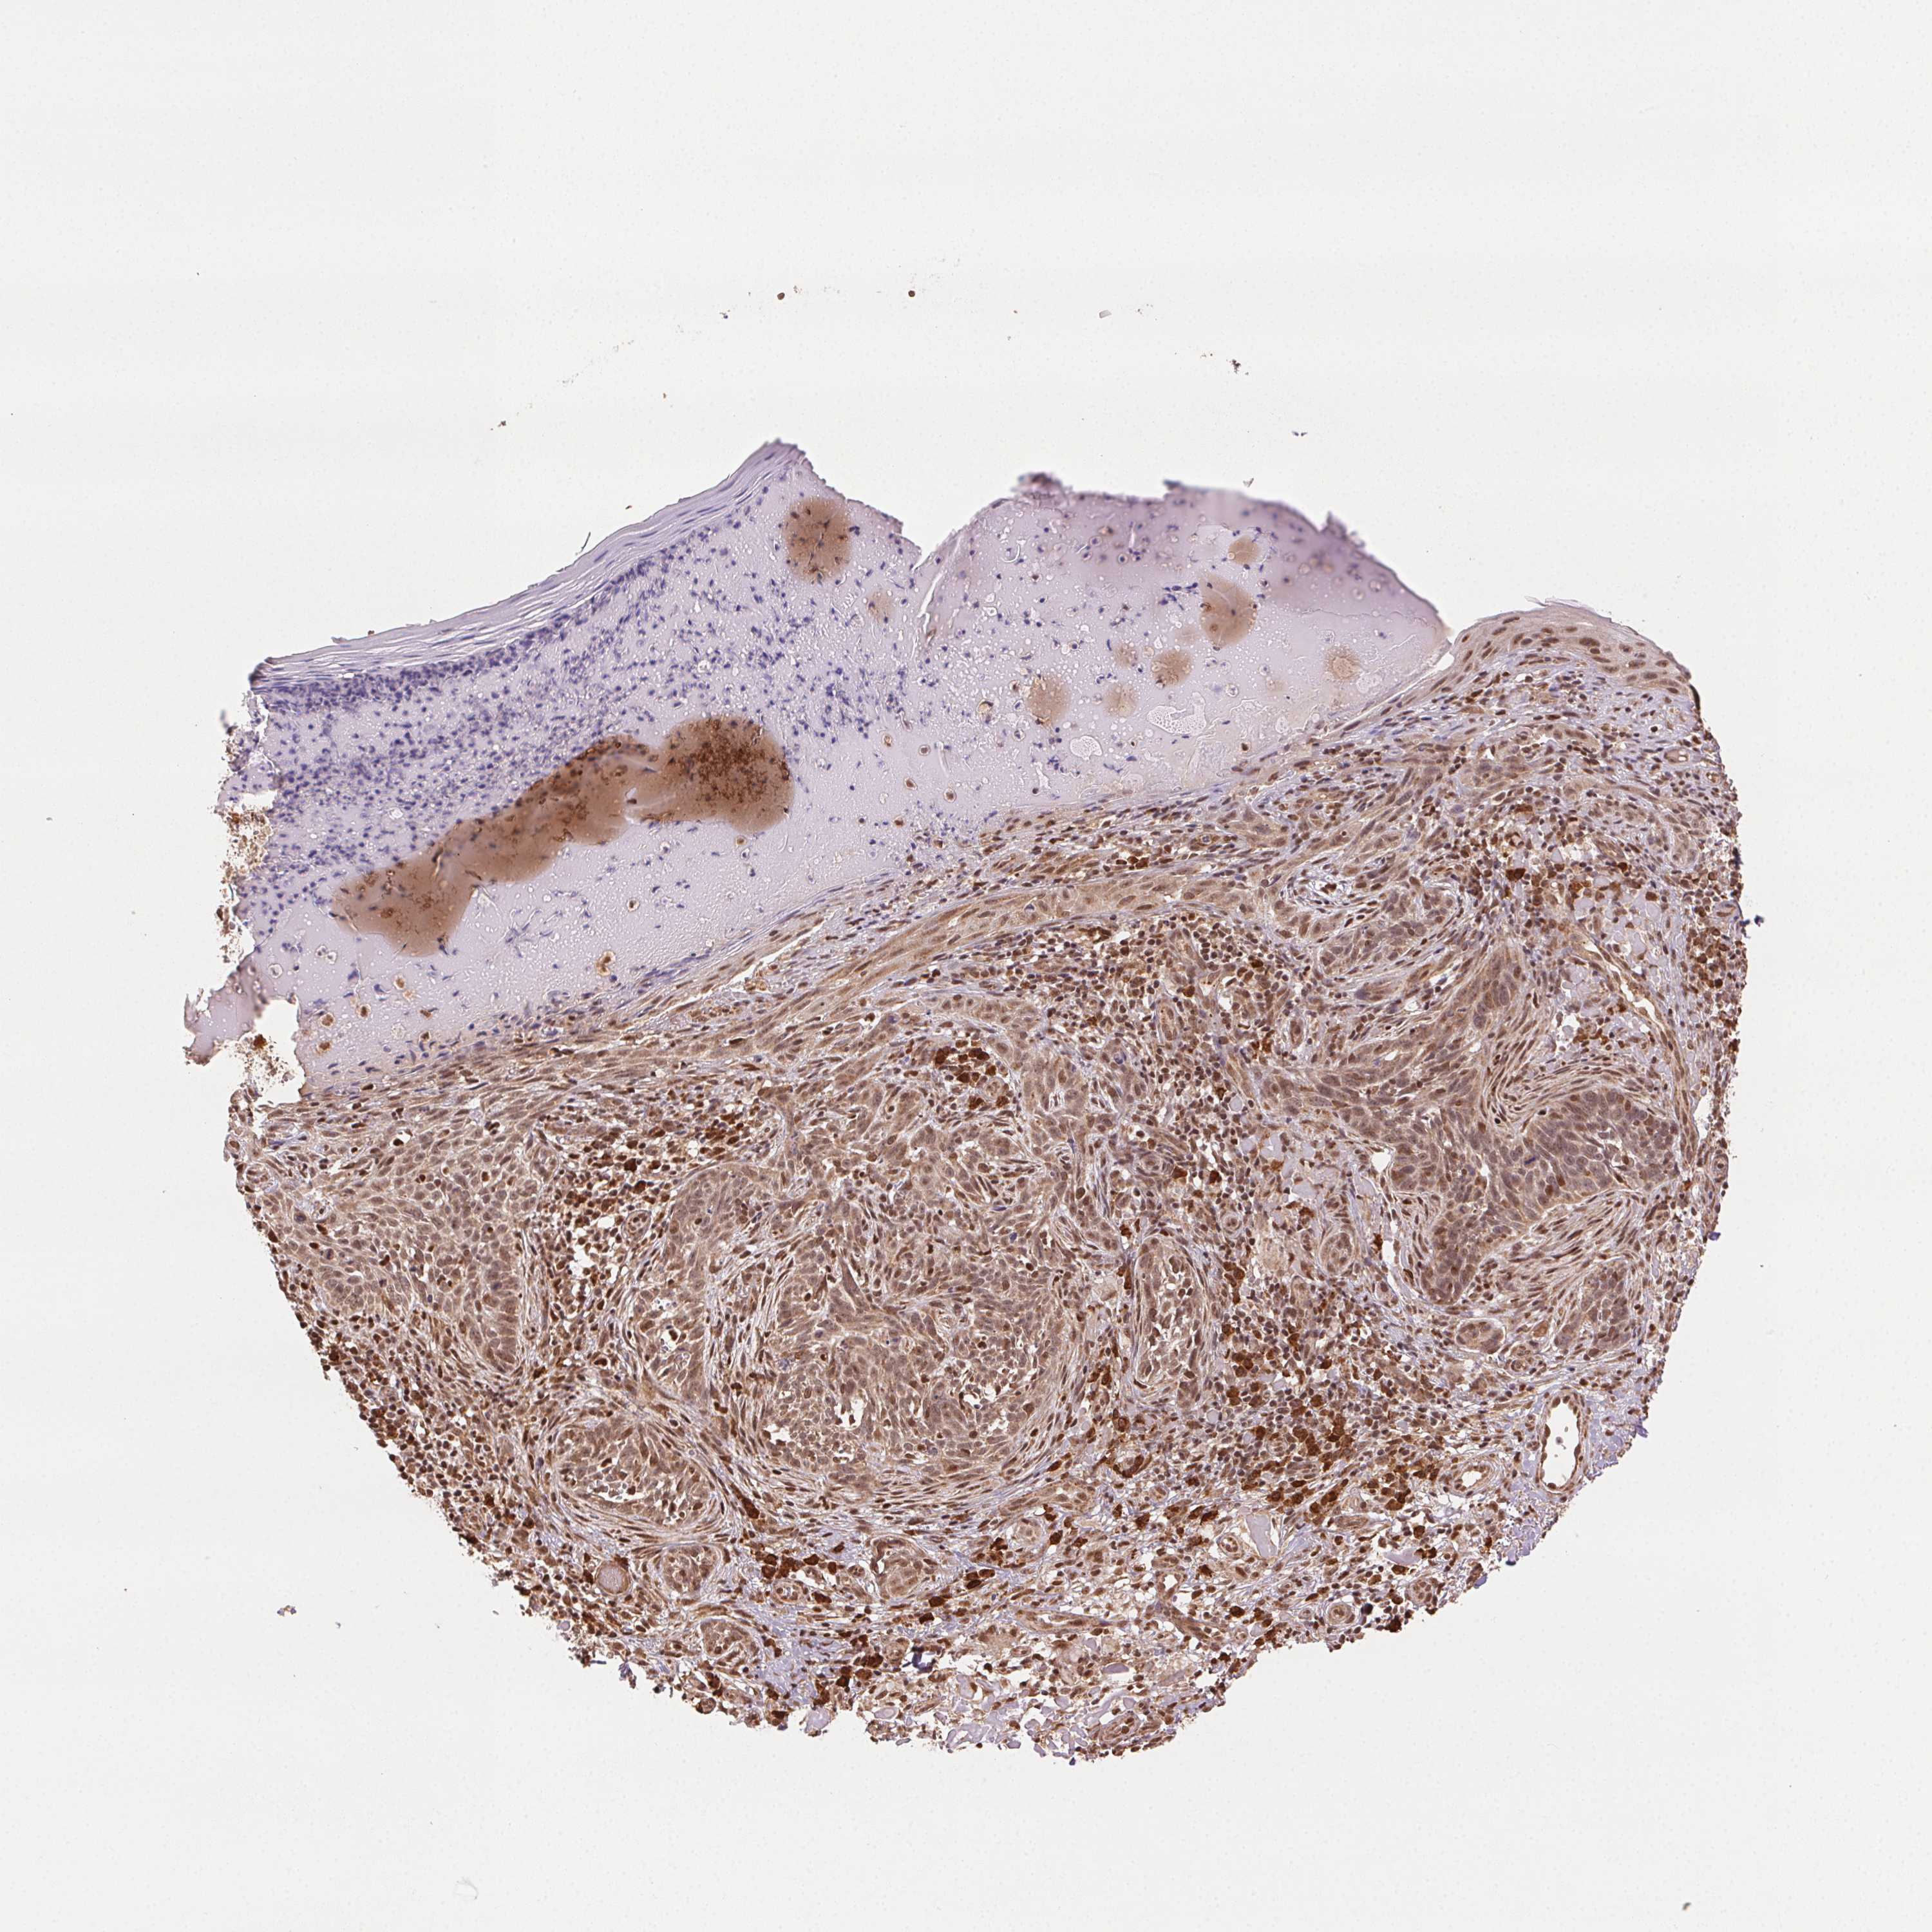

CANCER SKIN CANCER Show tissue menu

Basal cell and squamous cell cancer

SKIN CANCER - Protein expressioni

A mouse-over function shows sample information and annotation data. Click on an image to view it in a full screen mode. Samples can be filtered based on level of antibody staining by selecting one or several of the following categories: high, medium, low and not detected. The assay and annotation is described here.

Each image is clickable and will lead to virtual microscopy that enables deeper exploration of all samples and also displays staining intensity scores, fraction scores and subcellular localization as well as patient and tissue information for each sample.

Antibody HPA065044

Staining

High

Strong

Quantity

Location

Basal cell carcinoma

Squamous cell carcinoma, NOS